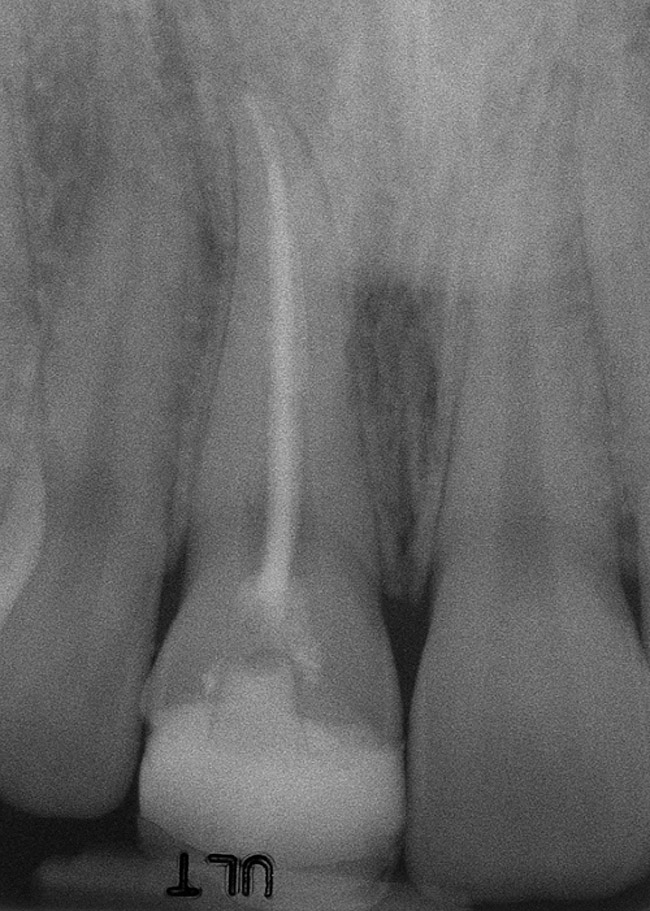

Figure 6a  Upper right central incisor, history of trauma, existing RCT and restoration unsatisfactory.

Figure 6a

Figure 6b  Upper right central incisor, history of trauma, existing RCT and restoration unsatisfactory.

Figure 6b

Figure 6c  Upper right central incisor, history of trauma, existing RCT and restoration unsatisfactory.

Figure 6c

Figure 6d Completed treatment: revised RCT, zirconium post/pressed ceramic core cemented with Panavia 21¬Æ Resin Cement (Kuraray Dental). All-ceramic full-coverage crown cemented with Kerr NX3 Nexus¬Æ Third Generation Dual Cure Resin cement. Implant therapy not indicated.

Figure 6d

Figure 6e  Completed treatment: revised RCT, zirconium post/pressed ceramic core cemented with Panavia 21¬Æ Resin Cement (Kuraray Dental). All-ceramic full-coverage crown cemented with Kerr NX3 Nexus¬Æ Third Generation Dual Cure Resin cement. Implant therapy not indicated.

Figure 6e

Figure 6f  Completed treatment: revised RCT, zirconium post/pressed ceramic core cemented with Panavia 21¬Æ Resin Cement (Kuraray Dental). All-ceramic full-coverage crown cemented with Kerr NX3 Nexus¬Æ Third Generation Dual Cure Resin cement. Implant therapy not indicated.

Figure 6f